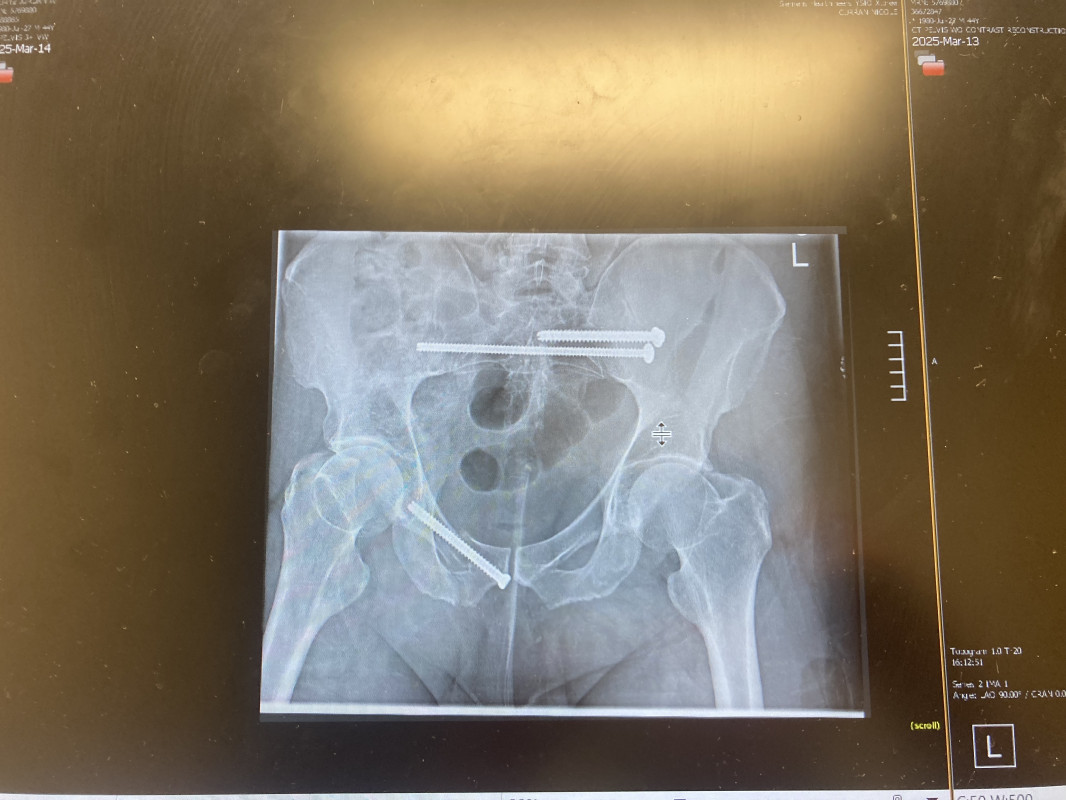

Fundraising to help get back on his feet to walk again from a shattered pelvis and extended stay in hospital with specialized surgery. All your support is greatly appreciated ; thanks to all family and friends and within allegheny health network for all efforts ongoing. Funds to help give back and to ease transition w more forward progress ; and humble thanks ahead.